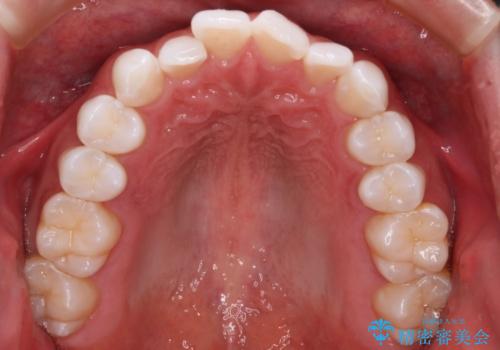

- 20代男性

- インビザライン

- がたつきが気になるとの事で来院されました。

目立たない装置で費用も抑えたいとの希望があったため、インビザラインにて治療をすることとなりました。

上下顎ともにIPR(歯と歯の間を削る処置)を行い歯並びを整える治療計画を立てました。

治療当初は、計画通りに治療が進むか心配でしたが、しっかりマウスピースを使用していただいたことで

治療期間も長引くことなく歯並びを綺麗に改善することが出来ました。

患者様の希望もあり、前歯の微調整で1回リファイメント(マウスピースの再発注)を行いました。